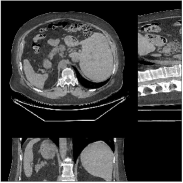

Fig.Β 8 shows the reconstructions (shown for the central axial, sagittal, and coronal planes in the 3D volume) for PWLS-EP with different regularization strengths , denoted as a multiplicative factor of the parameter value in Fig.Β 7. Fig.Β 9 shows the reconstructions for PWLS-ULTRA (with patch-based weights) with different parameter combinations. For the sagittal and coronal planes, we show the central out of axial slices. Larger regularization strengths would achieve more noise reduction but simultaneously lower spatial resolution in PWLS-EP and PWLS-ULTRA, e.g., compare Fig.Β 8 and Figs.Β 9(a) and (d). Larger values of would achieve lower sparsities and more noise reduction but potentially oversmooth the image, e.g., compare Figs.Β 9(c) and (d). Small values of may introduce additional spurious noise in the PWLS-ULTRA reconstruction (compare Figs.Β 9(a) and (b)). Fig.Β 11 shows profiles of chest reconstructions (plotted from the central axial slice) for the PWLS-EP and PWLS-ULTRA methods. The profile locations are shown in green lines in Fig.Β 7. Both PWLS-EP with regularization strength X and PWLS-ULTRA (with patch-based weights) in Fig.Β 9(a) have lower noise than the PWLS-EP with regularization strength X. Though the spatial resolution of PWLS-EP with regularization strength X is close to PWLS-ULTRA in the selected soft-tissue regions, PWLS-ULTRA reconstructs bone and spine areas with higher resolution, and preserves small features better (compare the zoomed-in areas in Fig.Β 8 and Fig.Β 9).